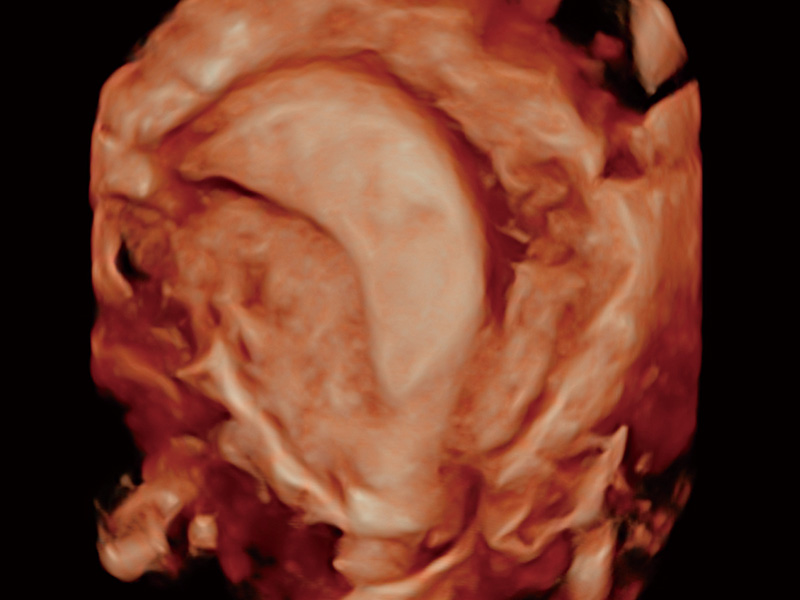

“生育问题”即关系民族复兴,也关系亿万家庭的幸福。随着婚育年龄推迟、社会压力增加等因素,越来越多人群也面临着“生不出、生不好”的问题。辅助生殖作为治疗不孕不育最有效的方法之一,也逐渐成为育儿新希望。而超声检查能为生殖需求人群的初诊评估提供宝贵的信息。 P20 Elite是db真人体育官网匠心打造的一款生殖应用型彩超。她继承db真人体育官网高端极光平台,突破性地将多款新型芯片及硬件模块进行整合,均衡了高端系统性能与小巧灵动机身。P20 Elite卓越的图像质量搭载专科探头,旨在为您提供全面的辅助生殖解决方案。

P20 Elite配备了丰富的生殖探头群和临床应用功能,在卵泡监测、穿刺取卵、胚胎移植、妊娠确认等领域,为生殖需求人群提供了新的临床机会,重新定义高端超声如何应用于生殖健康检查。